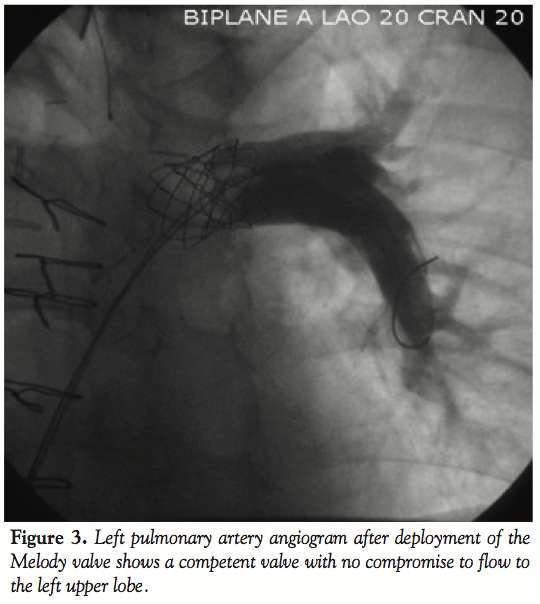

We then proceeded to evaluate the LPA for implantation of the Melody valve (Medtronic). An angiogram in the MPA/proximal LPA region showed occlusion of the proximal RPA and free pulmonary regurgitation with the proximal LPA measuring 18 mm, increasing to 20 mm prior to the origin of the left upper lobe pulmonary artery branch (Figure 1). The distance from the MPA/LPA junction to the origin of the left upper lobe pulmonary artery was confirmed at 26 mm. In order to test the compliance of the lesion and to better assess the size of the narrowest portion of the proximal LPA, a 25 mm x 5 cm Tyshak II balloon (B. Braun) was advanced to the proximal LPA and inflated at low pressure to 2 atm. The waist on the balloon measured 20 mm and the balloon remained in stable position during this inflation (Figure 2). The narrowest portion was at the MPA/proximal LPA, at the previous surgical suture line with the pulmonary artery homograft. We decided to deploy the Melody valve in this area using a 22 mm Ensemble Transcatheter Delivery System (Medtronic). A curved 0.035” Lunderquist Extra Stiff Wire Guide (Cook Medical) was placed in the distal LPA and the system was advanced with relative ease to the LPA where it was positioned. Multiple angiograms through the side port were performed to accurately position the valve and place it proximal to the origin of the left upper lobe pulmonary artery. The inner and outer balloons were inflated sequentially and then deflated. The outer balloon was then inflated to slightly higher pressure. There was a residual waist seen in the mid portion of the stent measuring about 20 mm at the origin of the LPA from the MPA. Pullback pressures demonstrated a 4 mm Hg systolic gradient from the distal LPA to the MPA across the valve. Repeat angiography showed excellent valve function with no compromise in flow to the left upper lobe branch pulmonary artery and no regurgitation (Figure 3). A transthoracic echocardiogram the next day confirmed excellent valve function with trivial regurgitation through the valved stent.